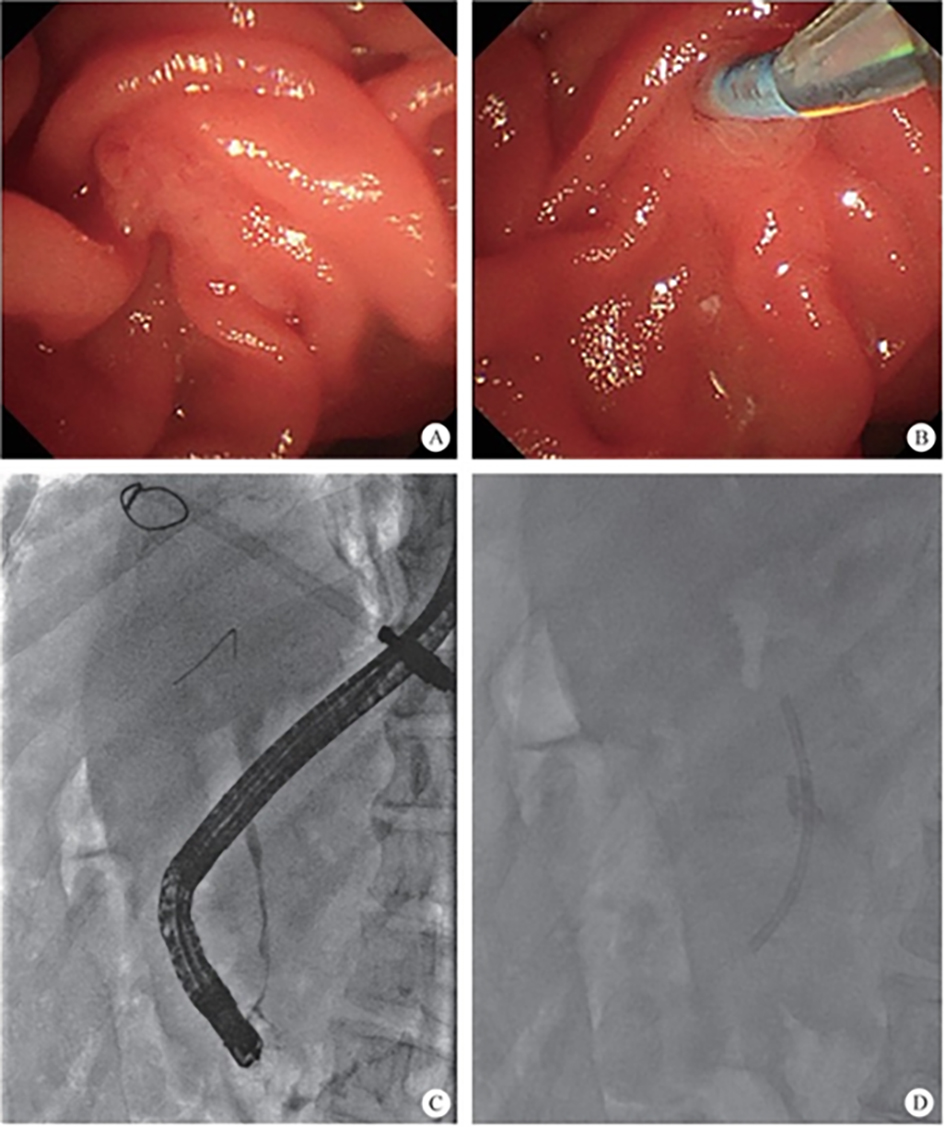

(2) Development of pancreaticobiliary endoscopy: endoscopic retrograde cholangiao-pancreatography (ERCP) has developed steadily for more than half a century, and finally blazed the visible field of the pancreaticobiliary diseases after the emergence of biliary and pancreatic vision equipment, which explored the diagnosis and treatment scope of the endoscope, making precision diagnosis and treatment become a reality. On that basis, a series of SMIS surgeries for biliopancreatic diseases have obtained decisive progress, including laser lithotripsy under direct choledochoscope with preserved sphincter, exploratory pancreatic duct with cholangiopancreatic vision system, super minimally invasive photodynamic therapy under the pancreatic duct, radiofrequency ablation of the bile duct under direct choledochoscope, direct choledochoscopy with a papillary support for cholecystolithiasis and extraction of biliary calculus, etc.

The normal common bile duct pressure is 10–15 mmHg (1 mmHg = 0.133 kPa) higher than that of the duodenum, but the basal pressure of the sphincter of Oddi is about 4 mmHg higher than that of the pancreatic biliary system, so that the sphincter of Oddi can effectively prevent the regurgitation of duodenal contents and avoid gastrointestinal bacterial retrograde infection. EST is usually performed before duodenal papillary intubation, which damages the integrity of the sphincter of Oddi, leading to sphincter relaxation and a loss of the anti-reflux physiological function. In 2020, a study was conducted to investigate the feasibility and effectiveness of duodenoplasty to restore the function of the sphincter of Oddi. The study prospectively included 30 patients who had undergone EST lithotomy and duodenal papilloplasty; 80% of patients had a basal pressure of the sphincter of Oddi after duodenal papilloplasty >10 mmHg, and the pressure parameter was resumed after the operation, and was unrelated to the healing process. Postoperative mild pancreatitis occurred in six cases, and a recurrence of the stone in one case. Studies have shown that duodenal papilloplasty can restore the basal pressure of the sphincter of Oddi, thus restoring its anti-reflux function and possibly preventing the reappearence of gallstones and cholangitis.

The intrahepatic bile duct is the relative blind area of SpyGlass. The treatment of intrahepatic bile ducts by retrograde transpancreatobiliary endoscopy can avoid the trauma of surgical choledochoscopy and sinus infection caused by percutaneous choledochoscopy. However, there are still few reports on the diagnosis and treatment of intrahepatic bile ducts by choledochoscopy in China and abroad, and they only concern grade-I and II intrahepatic bile ducts, even if currently the surgical choledochoscopic fiber can enter directly intrahepatic bile ducts above grade IV. In 2021, a study evaluated the effect of SpyGlass on grade-I and II intrahepatic bile duct lithotomy, whereas laser lithotripsis is performed for large or impacted gallstones at the same time. The results showed that the diagnostic rate of SpyGlass was 97.14%, the success rate of one-time lithotomy was 85.71%, the occurrence rate of complication was 8.57%, the postoperative residual stone rate was 14.28%, showing that SpyGlass can effectively diagnose and treat intrahepatic bile duct stones. But so far a multi-center study is still lacking to support its clinical promotion and application. In addition, SpyGlass can also be used to remove gallstones through the gallbladder duct while preserving it, with a high rate of stone removal, while being less traumatic, with rapid recovery and effective resumption of gallbladder function.